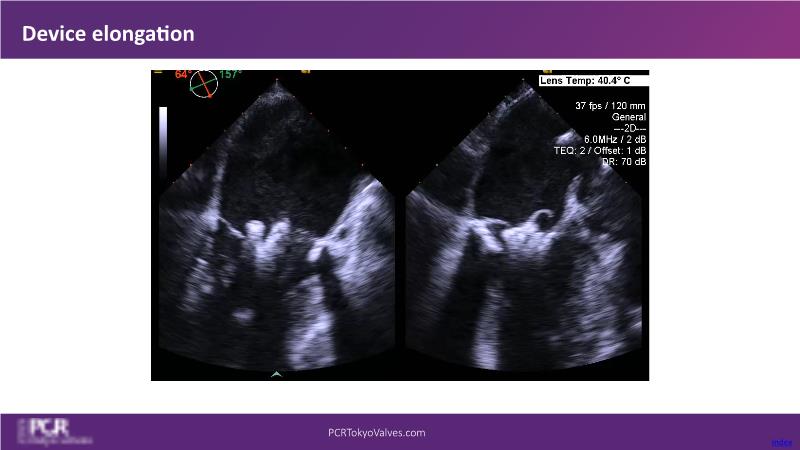

Watch this session to get an overview of a new TEER device, follow the step-by-step procedure related to initial experiences with this device for a Japanese patient with degenerative mitral regurgitation, learn about the latest data from RCT and registries, and follow discussions of challenging TEER cases!

- To learn procedural step-by-step of novel device